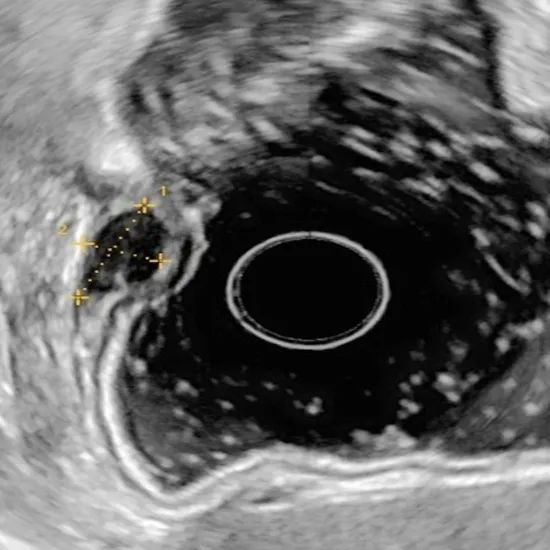

▲超声内镜定位

经过详实有效的术前沟通,取得患者及家属知情同意并签字,做好充分术前评估及准备后,患者进行了手术,首先由消化内镜团队的陈好医生对患者胃部肿物进行超声内镜进行术前定位,随后由郑中文、黄懿波医生实施胃镜下胃肿物挖除术(ESE),在李捷壮、刘烈辉主任的技术指导下,超声确认肿瘤起源于固有肌层后,立即建立黏膜下隧道完整剥离肿物,全过程顺利,手术历时30分钟,整个诊疗过程不足60分钟,术后不到20分钟患者苏醒,无诉不适,体验感极佳!

1.双镜合璧技术。①超声内镜:5MHz高频探头实现"肿瘤CT级扫描",精准判断间质瘤层次(黏膜肌层/固有肌层)。②ESE技术:黏膜下隧道建立+完整剥离,保留胃壁及胃粘膜面的完整性(图示手术步骤分解)。